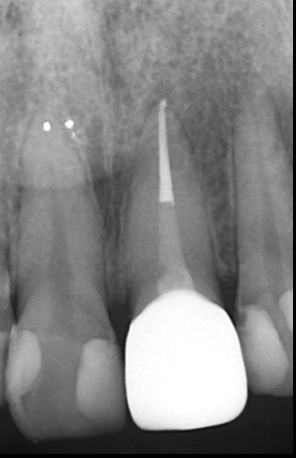

デンタルX線写真

デンタルX線写真(治療後)